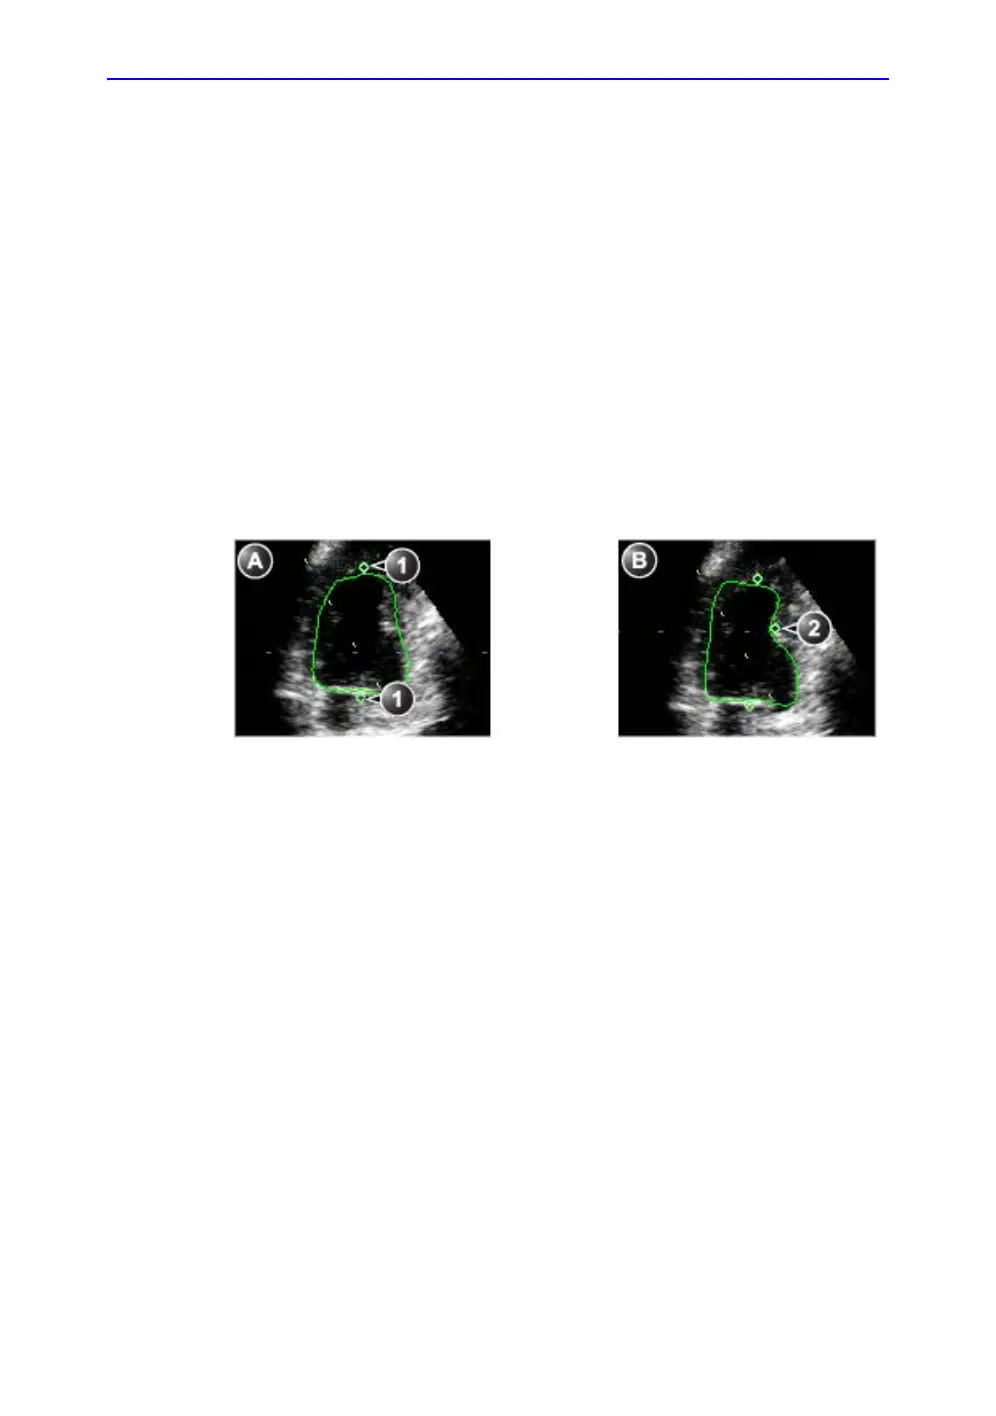

Figure 8-29. Contour adjustment

a. Original contour b. Modified contour

1. Original attracting points 2. Added attracting point

The contour detection should be checked. If the contour

detection is not optimal, it can be adjusted by adding attracting

points to the contour. An attracting point will pull the contour

toward that point.

A point is added and the contour is modified (Figure 8-29).